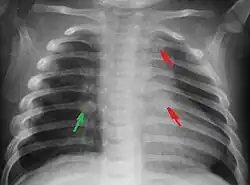

Most nations with child abuse laws deem the deliberate infliction of serious injuries, or actions that place the child at obvious risk of serious injury or death, to be illegal.[36] Bruises, scratches, burns, broken bones, lacerations—as well as repeated "mishaps", and rough treatment that could cause physical injuries—can be physical abuse.[37] Multiple injuries or fractures at different stages of healing can raise suspicion of abuse.

Battered-child syndrome

C. Henry Kempe and his colleagues were the first to describe the battered-child syndrome in 1962.[40] The battered-child syndrome is a term used to describe a collection of injuries that young children sustain as a result of repeated physical abuse or neglect.[41][42] These symptoms may include: fractures of bones, multiple soft tissue injuries, subdural hematoma (bleeding in the brain), malnutrition, and poor skin hygiene.[42][43]

Children suffering from battered-child syndrome may come to the doctor's attention for a problem unrelated to abuse or after experiencing an acute injury, but when examined, they show signs of long-term abuse.[44] In most cases, the caretakers try to justify the visible injuries by blaming them on minor accidents.[44] When asked, parents may attribute the injuries to a child's behaviour or habits, such as being fussy or clumsy. Despite the abuse, the child may show attachment to the parent.[44]

Physical

The immediate physical effects of abuse or neglect can be relatively minor (bruises or cuts) or severe (broken bones, hemorrhage, death). Certain injuries, such as rib fractures or femoral fractures in infants that are not yet walking, may increase suspicion of child physical abuse, although such injuries are only seen in a fraction of children suffering physical abuse.[90][91] Cigarette burns or scald injuries may also prompt evaluation for child physical abuse.[92]